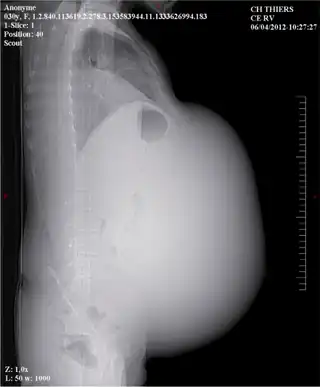

| Scout view of the abdominopelvic mass (top), thoracic axial CT-scan showing a right pleural effusion (bottom) | |

In medicine, Meigs's syndrome, also Meigs syndrome or Demons–Meigs syndrome, is the triad of ascites, pleural effusion, and benign ovarian tumor (ovarian fibroma, fibrothecoma, Brenner tumour, and occasionally granulosa cell tumour).[1][2][3] Meigs syndrome resolves after the resection of the tumor. Because the transdiaphragmatic lymphatic channels are larger in diameter on the right, the pleural effusion is classically on the right side. The causes of the ascites and pleural effusion are poorly understood.[1] Atypical Meigs syndrome, characterized by a benign pelvic mass with right-sided pleural effusion but without ascites, can also occur. As in typical Meigs syndrome, pleural effusion resolves after removal of the pelvic mass.[1]